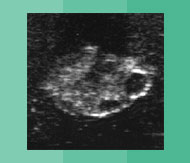

Besamung Verhalten Verhalten in der Vorbrunst In der Vorbrunst beginnt das Tier unruhig zu werden (Flehmen, Kopf auflegen). Brünstig werdende Tiere legen oft den Schwanz zur Seite, insbesondere, wenn sie von anderen Tieren beschnuppert werden. Für eine Besamung ist es zu früh, aber man muss gut beobachten! Verhalten in der Brunst Zu Brunstbeginn kann es rund um die brünstig werdende Kuh sehr unruhig werden. Besonders auf der Weide ist das gut sichtbar. Mitte der Brunst: Die Kuh duldet andere Kühe, wenn diese ihr aufspringen. Sie zeigt den Duldungsreflex. Für eine Besamung ist es noch zu früh! Aber die Kuh kann bereits beim Besamer angemeldet werden. Im Stall kann man hochbrünstige Tiere am stieren Blick, gestellten Ohren und durchgekrümmten Rücken manchmal gut erkennen. Verhalten in der Nachbrunst Jetzt is der ideale Besamungszeitpunkt! Das Tier wird wieder ruhiger und duldet andere Tiere nicht mehr beim Aufsprungversuch. Aber: Beim Abbluten ist es zu spät für die Besamung! Verhalten in der Zwischenbrunst In der Zwischenbrunst verhalten sich die Tiere unauffällig. 2-3 unruhige Phasen von einigen Stunden sind möglich. Eine Besamung macht hier keinen Sinn! Eierstock Eierstock in der Vorbrunst Der Gelbkörper bildet sich zurück. Das dominate Eibläschen hat einen Durchmesser von gut 1cm. Das Eibläschen ist glatt und prall („uhrglasartig“). Der Eierstock in der Brunst Das Eibläschen wächst in kurzer Zeit heran und ist prall. Der Gelbkörper von der letzten Brunst kann noch spürbar sein. Das Eibläschen erreicht einen Durchmesser von ca. 1.5 bis 2 cm und wird weicher. Jetzt hat das Eibläschen seine maximale Grösse erreicht. Kurz bevor es springt, wird es weich. Der Eierstock in der Nachbrunst Zu Beginn der Nachbrunst springt das Eibläschen. Das Eibläschen wird vom Eileitertrichter aufgefangen. Im Eileiter findet die Befruchtung durch den Samen statt. Der Eierstock in der Zwischenbrunst Der Gelbkörper hat oft eine Form wie ein Champagnerzapfen. Während eines Zyklus können sich 1-2 Eibläschen auf dem Eierstock an- und wieder zurückbilden. Der Gelbkörper bildet sich zurück, wenn von der nichtträchtigen Gebärmutter Prostaglandin gebildet wird. Gebärmutter & Scheide Gebärmutter u. Scheide in der Vorbrunst Die Spannung in der Gebärmuttermuskulatur nimmt zu. Der Muttermund beginnt sich zu öffnen. Die Scheidenschleimhaut wird wieder feucht und rötet sich. Gebärmutter u. Scheide in der Brunst Die Gebärmuttermuskulatur zieht sich in der Brunst maximal zusammen. Die Gebärmutter ist daher klein und fest. Die Schleimhaut in der Scheide erscheint blassrosa und feucht und der Muttermund kann deutlich offen sein. Fadenziehender klarer Schleim kommt aus der Scheide. Gebärmutter u. Scheide in der Nachbrunst Die Muskulatur der Gebärmutter entspannt sich. Das Abbluten kann als guter Anhaltspunkt auf dem Brunstkalender festgehalten werden. Die Schwellung der Schamlippen geht zurück. Gebärmutter u. Scheide in der Zwischenbrunst Die Muskulatur der Gebärmutter ist entspannt und wenig kontrahiert. Der Muttermund ist fest verschlossen und die Scheidenschleimhaut ist wenig feucht und blass. Die Schamlippen sind gefältelt. Hormone Hormone in der Vorbrunst Hormone aus dem Zwischenhirn (GnRH) und der Hirnanhangsdrüse (FSH) werden in die Blutbahn abgegeben. Das follikelstimulierende Hormon FSH bewirkt die letzte Reifung des dominanten Eibläschens. Das dominante Eibläschen produziert das Brunsthormon (Östrogen). Hormone in der Brunst Das Brunsthormon wird vom Eibläschen produziert. Das Brunsthormon ist verantwortlich für das typische Verhalten der Kuh in der Brunst und die sichtbaren Veränderungen am Geschlechtstrakt. Der Anstieg des luteinisierendem Hormons LH führt zum Eisprung am Ende der Hauptbrunst oder bereits zu Beginn der Nachbrunst. Hormone in der Nachbrunst Das luteinisierende Hormon bewirkt den Eisprung und die Bildung von Gelbkörpergewebe. Die Produktion vom Trächtigkeitshormon beginnt. Der Spiegel vom Brunsthormon ist wieder tief. Hormone in der Zwischenbrunst Der Gelbkörper bildet im Zyklus während ca. 14 Tagen das Trächtigkeitshormon Progesteron. Bei einer Trächtigkeit bildet die Gebärmutter dank Signal des Embryos um den 16. Zyklustag kein Prostaglandin F2alpha und der Gelbkörper bleibt bestehen. Ohne Befruchtung bildet die Gebärmutter Prostaglandin F2alpha, der Gelbkörper geht zu Grunde und ein neuer Zyklus beginnt. Bedienungsanleitung Vorbrunst Brunst Nachbrunst Zwischenbrunst